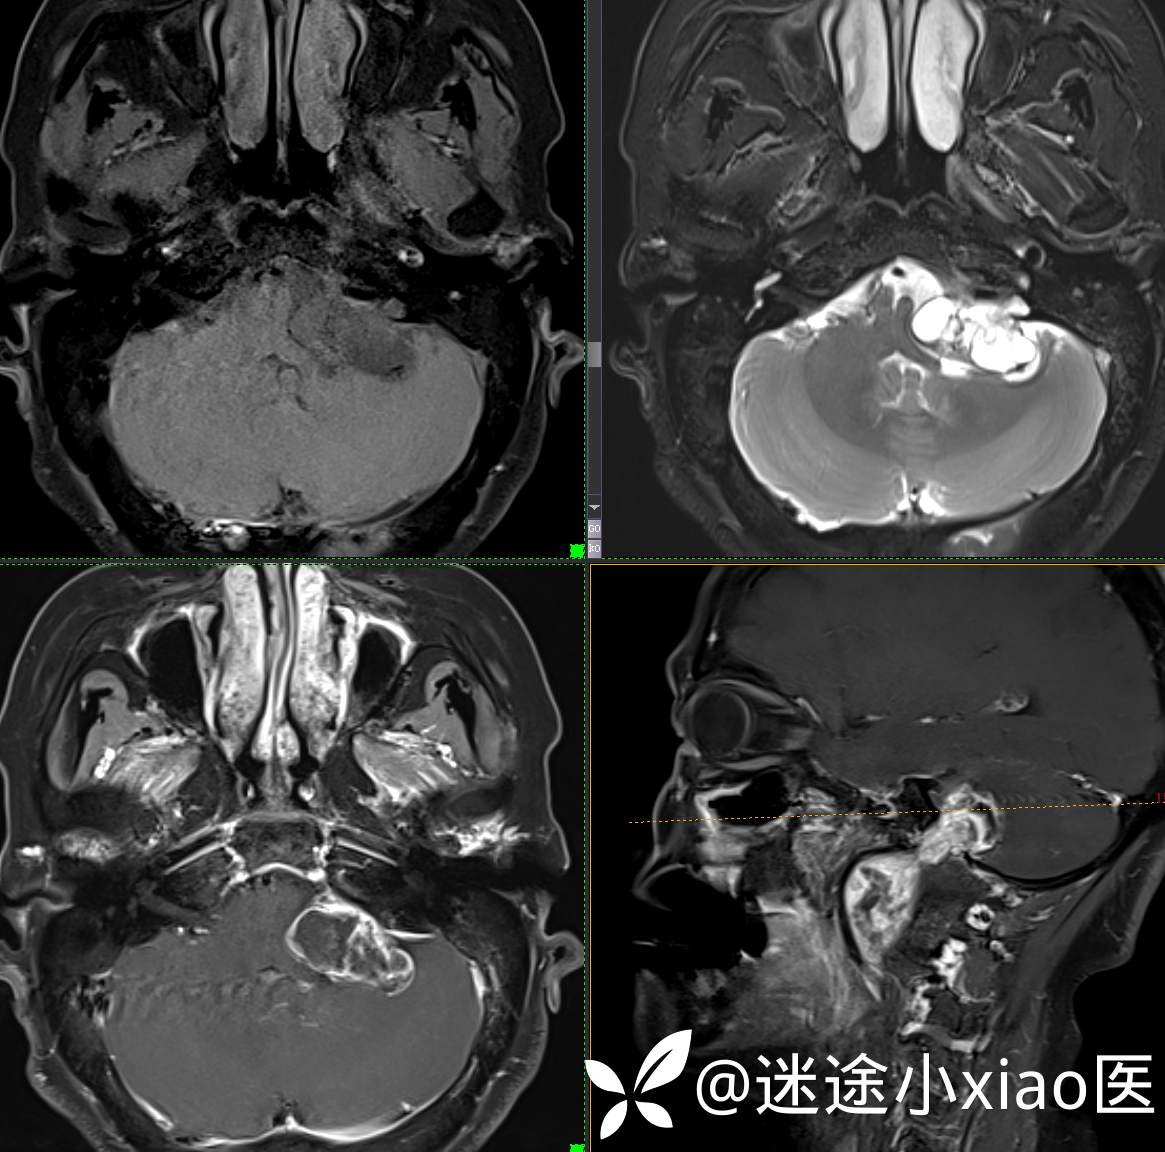

头颈组17:颈静脉孔区占位,副神经节瘤?神经鞘瘤?脑膜瘤?

患者性别:女

患者年龄:57岁

主 诉:  声音嘶哑进食困难伴左侧颌部麻木半年

现病史:  【患者半年前无明显诱因出现声音嘶哑,进食困难,只能进食糊状食物,伴有恶心呕吐,无明显头痛头晕,未加重视。